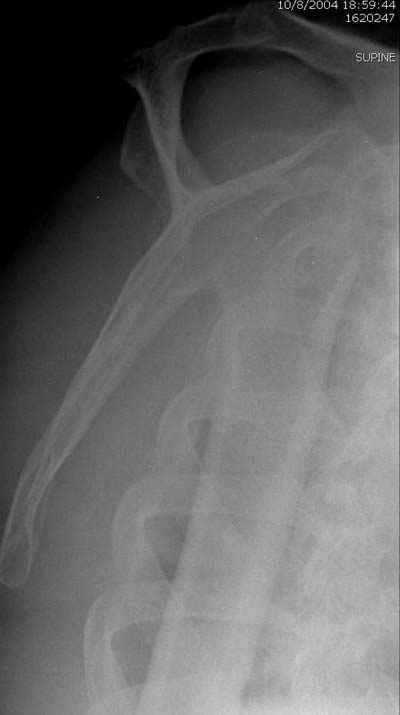

Спасибо за презентацию вашего случая. Две недели назад у меня был больной с переломовывихом плеча , правда, 4 недельной давности :-((( больной из отдаленной деревни). Закрыто сделать ничего не удалось естественно, при попытке открытого вправления головки она *рассыпалась* на фрагменты и суставной хрящ представлял из себя egg shell, поэтому пришлось ограничиться удалением фрагментов головки и физиотерапией. При таких ситуациях артропластика показана, но к сожалению нет такой возможности в местном госпитале - только в частном :-((